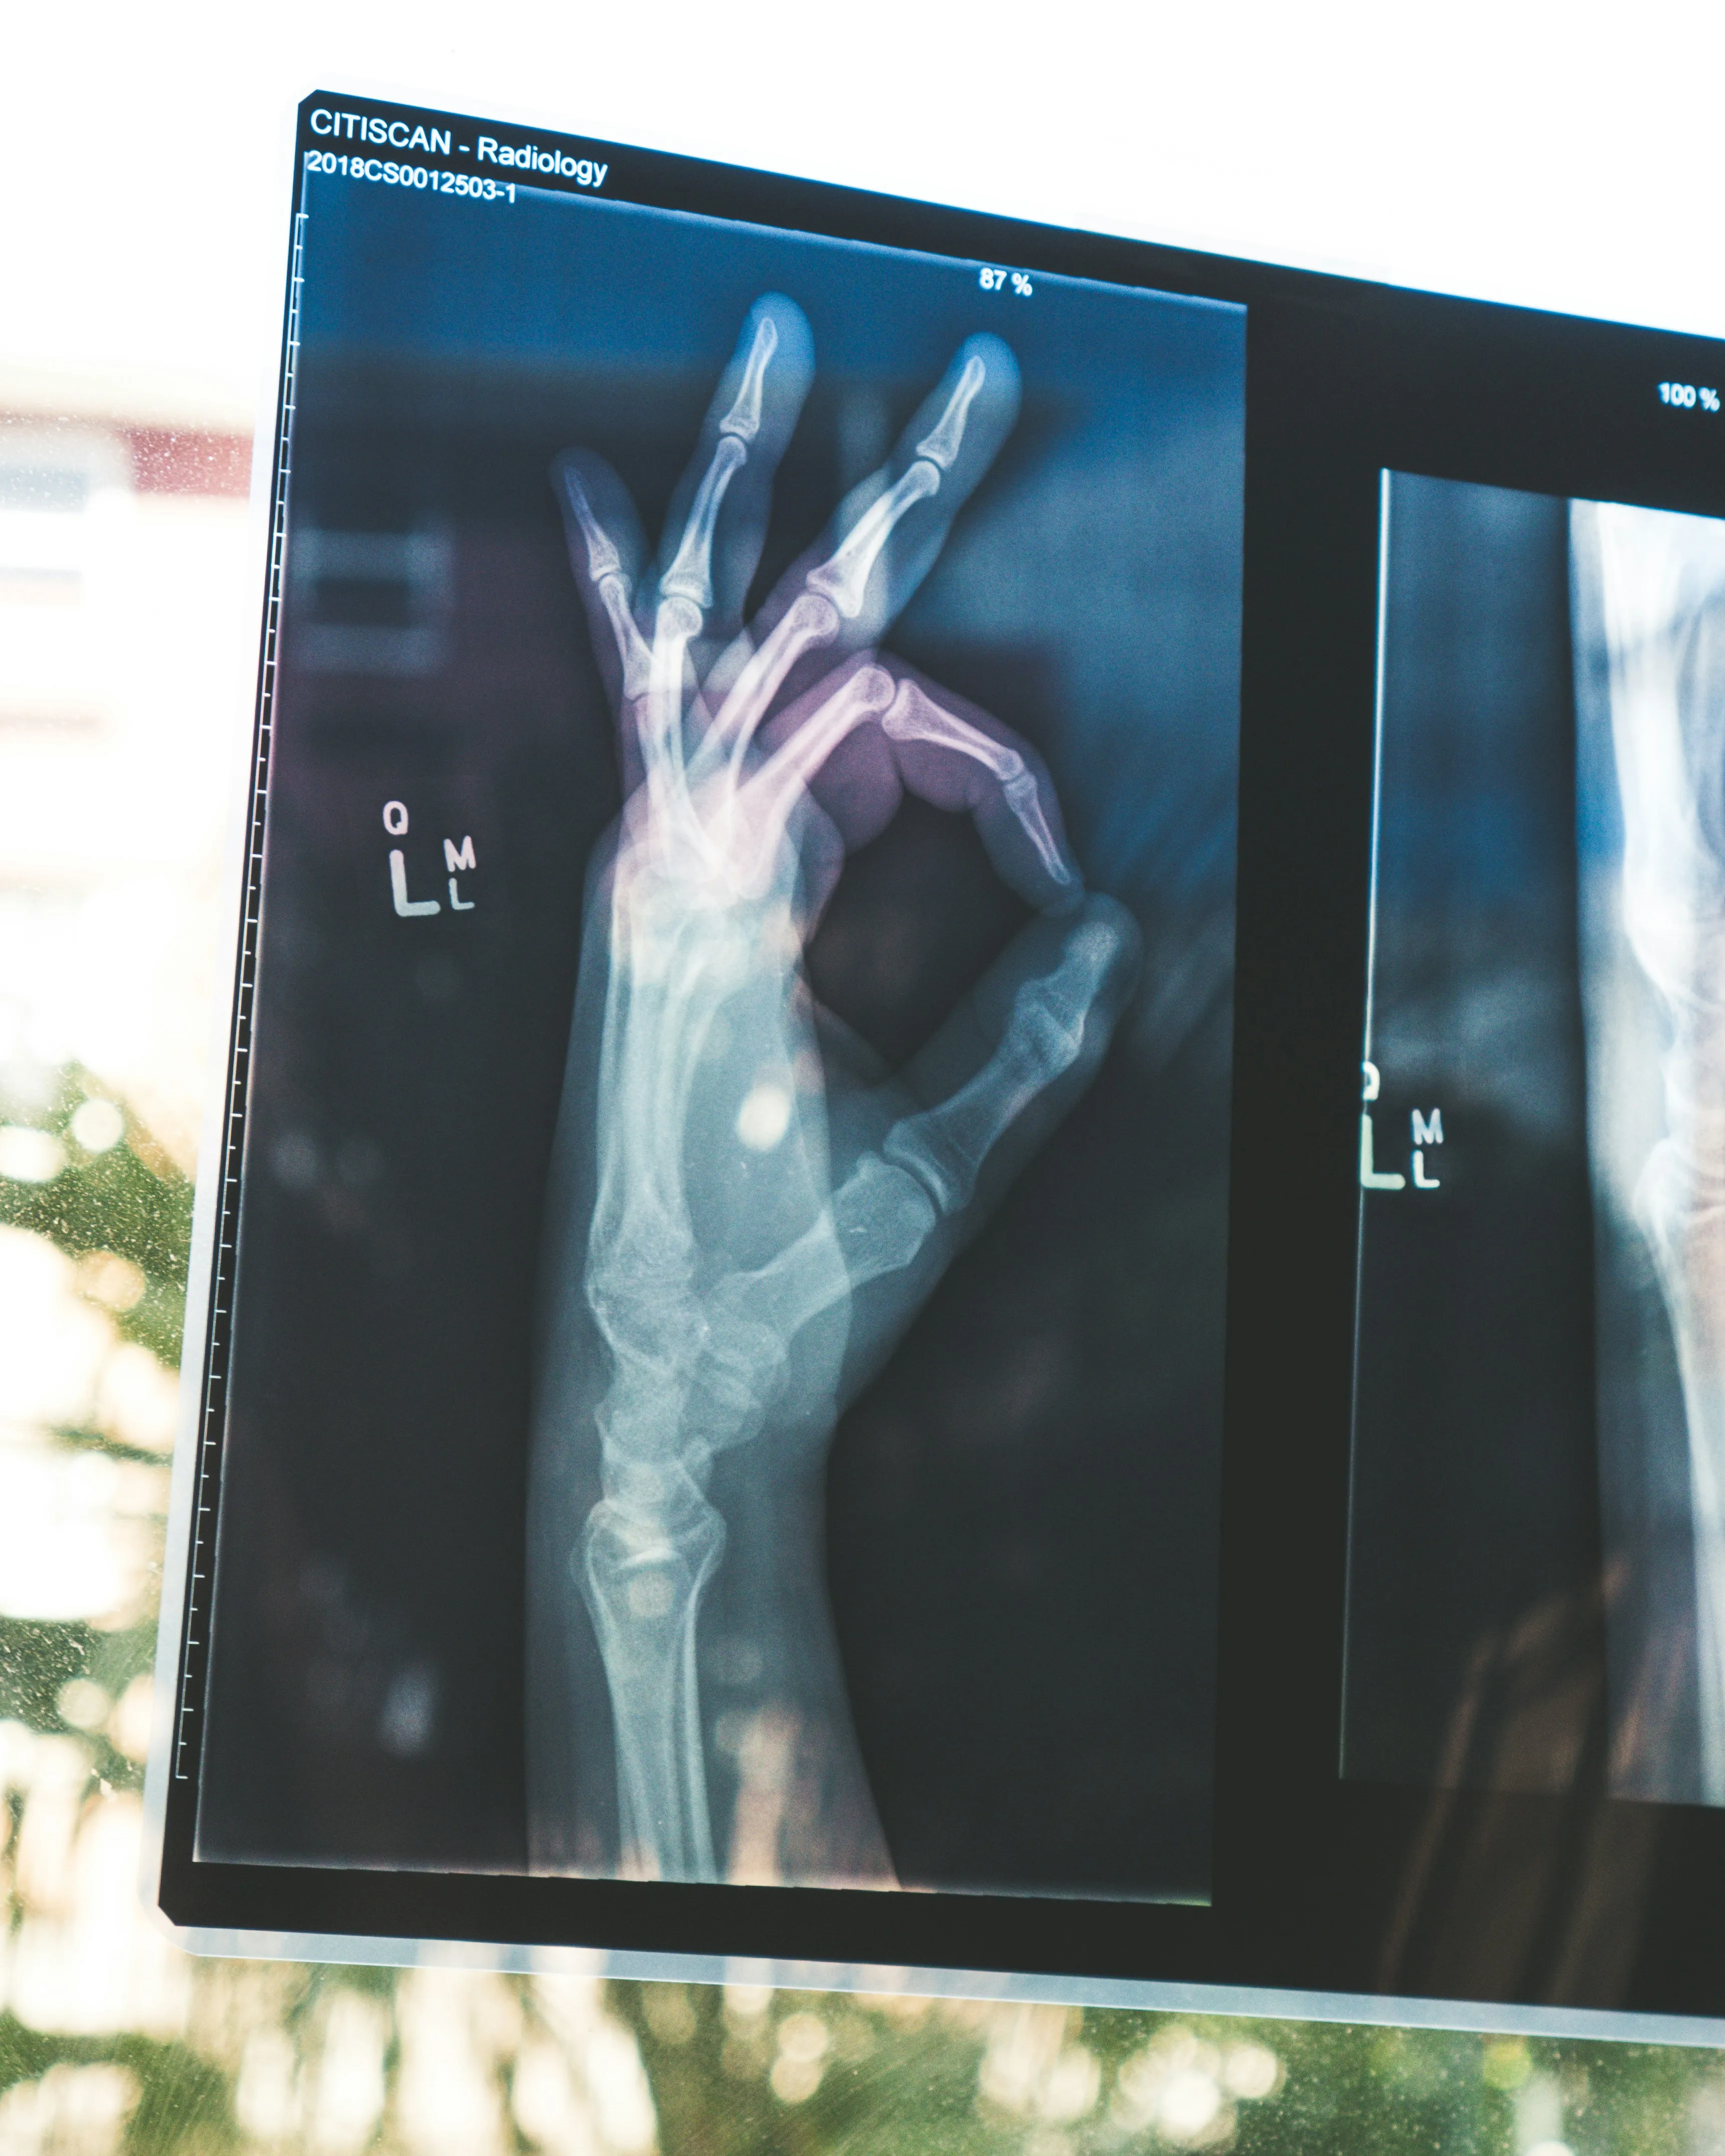

Rayos X digitales en pantalla para revisión diagnóstica